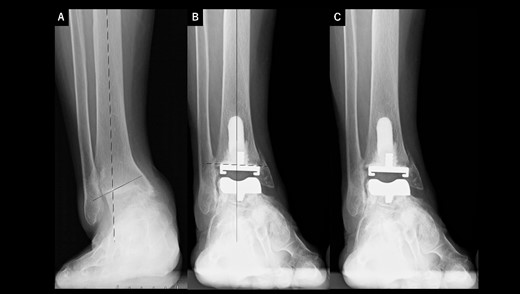

A 75-year-old woman with end-stage ankle OA and severe ankle joint pain and gait dysfunction had a JSSF ankle/hindfoot scale score of 42 points. Talar tilt showed 21° varus (Fig. 3A). She underwent TAA with medial malleolar osteotomy without internal fixation, and the tibial component was placed in the 4° valgus position, unlike the other two cases (Fig. 3B). At present, 5 years after TAA, she can walk for more than 2 hours and feels no pain around the ankle. There is no evidence of prosthesis loosening even though incomplete bone union at the osteotomy site is evident (Fig. 3C).

Radiographs of preoperative weight-bearing radiograph of the antero-posterior ankle joint in Case 3. (A) Preoperative. Talar tilt is 21° varus. Opening of the lateral gutter is seen. (B) One month after surgery. Medial malleolar osteotomy without internal fixation and the tibial component placed in the 4° valgus position, unlike the other two cases. The lateral gutter is closed. (C) Five years after surgery. There is no evidence of prosthetic loosening, even though incomplete bone union at the osteotomy site is seen. The lateral gutter is still closed.